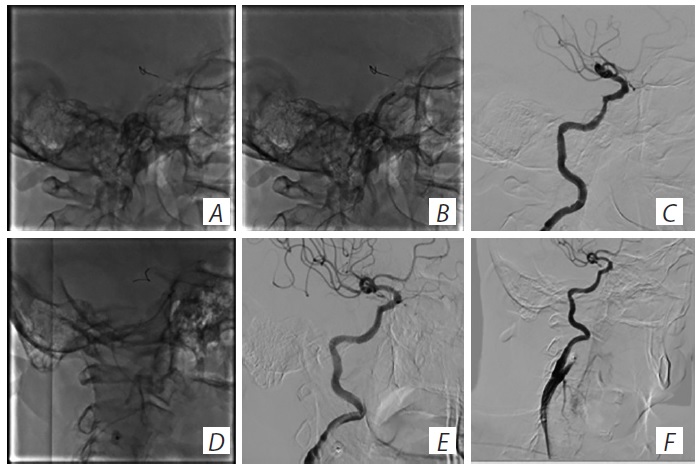

По окончании стентирования ВСА пациенту проведена ангиография ПА, выявлены стеноз правой ПА до 30%, устьевой стеноз левой ПА до 80% (рис. 7, А, В). Послеоперационный период — без осложнений. На момент выписки неврологический дефицит составил по NIHSS 0 баллов, по модифицированной шкале Рэнкина — 0 баллов.

Рис. 7. Ангиография и стентирование левой ПА. А — стеноз правой ПА 30%; В — стеноз левой ПА до 80%; С — ангиография перед стентированием левой ПА; D — стентирование левой ПА. / Fig. 7. Left renal artery angiography and stenting. А — right renal artery stenosis 30%; В — left renal artery stenosis up to 80%; С — pre-stenting left renal artery angiography; D — left renal artery stenting.

Учитывая сохранение устойчивой артериальной гипертензии, принято решение о выполнении пациенту стентирования ПА по двум основным критериям:

a) устойчивая артериальная гипертензия на фоне трёхкомпонентной ангигипертензивной терапии;

б) расположение стеноза ПА в устьевой зоне, что в дальнейшем не позволяет сформировать коллатеральный внутрипочечный кровоток при развитии ишемии из-за прогрессирования стеноза [25].

После выписки из неврологического отделения ввиду сохранения резистентной артериальной гипертензии пациент переведён в отделение сосудистой хирургии для стентирования левой ПА (рис. 7, C, D).